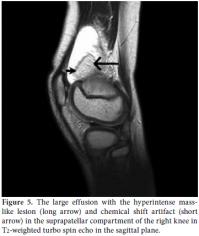

Magnetic resonance imaging revealed a large effusion and numerous frond-like projections which were prominent in the suprapatellar compartment of right knee. The intensity of these frond-like synovial projections, which were suppressed in fatsaturated sequences, was similar to the intensity of fat (Figures 2a, b). An effusion and a mass-like lesion were also detected in the popliteal bursa of the right knee. (Figures 3a, b) In addition, mild osteochondral changes occurred in both knees which were more pronouced on the right side (Figure 2a). Suprapatellar effusion was also detected in the left knee. No meniscal or ligament pathology was detected in either knee.

X-rays of the knees revealed minimal degenerative changes. Sonographic examination of both knees was performed by the EUB 6000 (Hitachi Medical Systems, Japan) with a high frequency linear array probe, and this revealed villous hyperechoic structures projecting into the suprapatellar effusion and a hyperechoic pseudo-mass lesion in the suprapatellar bursa in the right knee (Figure 4). Magnetic resonance imaging was performed using a 1.5 Tesla MR unit (Intera, Philips Medical Systems, the Netherlands) with an extremity coil for knee studies. The sequence included T1- and T2-weighted turbo spin echo (TSE) images in the fat-suppressed Short Tau Inversion Recovery (STIR) sequence in the axial, coronal, and sagittal planes. Magnetic resonance imaging revealed a large effusion (Figure 5), a hyperintense masslike lesion, and numerous frond-like projections in the suprapatellar compartment of the right knee (Figure 6a). The intensity of these frond-like synovial projections and the mass-like lesion, which were suppressed in the fat-saturated STIR sequences, was similar to the intensity of fat (Figure 6b). Chemical shift artifact was also detected (Figure 5). The signal intensities of these lobules were isointense with fat on the T1- and T2-weighted TSE images. These findings confirmed the fatty nature of the lesion and led us to the diagnosis of LA in the right knee. There were also mild osteochondral changes in both knees prominent in the right side. No meniscal or ligament pathology was detected in either knee.